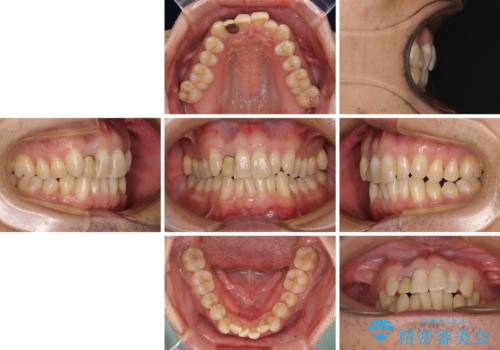

- 前歯のデコボコを気にして来院された患者様です。

目立たない装置で手軽に治したいとのことで、インビザラインにて矯正治療を行うこととしました。

前歯のクラウンは変色が著しいため、矯正治療後にオールセラミッククラウンにて補綴治療を行うこととしました。